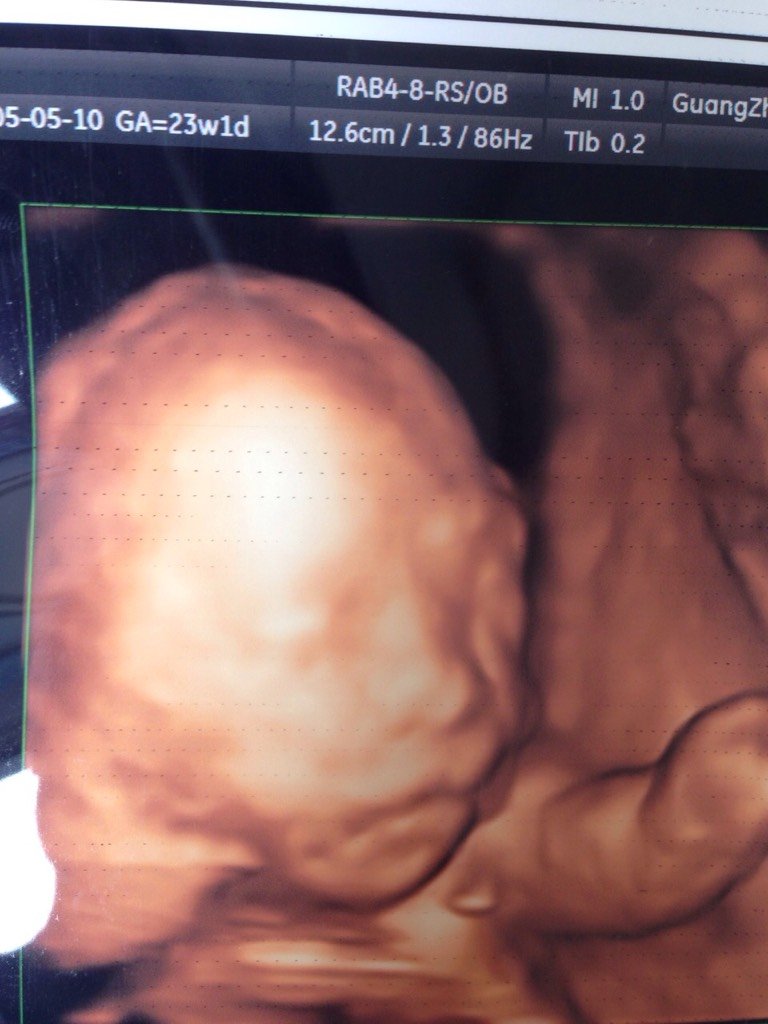

大家好,能不能帮我看看我家宝宝四维嘴唇是不是有问题啊,会不会是兔唇?

您好,看图貌似没事,您可以看一下彩超报告单上有没有写口唇连续,写的话一般没问题

肯定写的有 你没有仔细看, 四维彩超要写手脚嘴鼻的 整个身体结构都会写清楚的